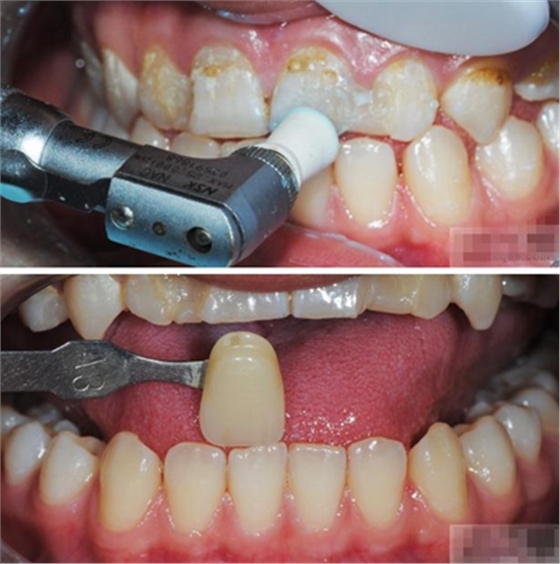

【比色】清潔牙面

比色

談到比色 要考慮天然牙:亮度 、飽和度、色相 、透明度、半透明度 ····

【基牙預(yù)備】樹(shù)脂貼面平齊牙齦邊緣是最佳設(shè)計(jì),或者使用齦上邊緣。

樹(shù)脂貼面平齊牙齦邊緣是最佳設(shè)計(jì),或者使用齦上邊緣

制備量問(wèn)題:1-2種顏色,需要0.3mm牙體預(yù)備

3-5種顏色,需要0.5mm牙體預(yù)備 5種以上的顏色,需要0.7-1.0mm牙體預(yù)備

釉質(zhì)邊緣要用橡皮輪拋光

拋光可以去除懸釉。這樣經(jīng)過(guò)車針打磨過(guò)的釉質(zhì)表面會(huì)更加均一,形成良好的邊緣封閉。